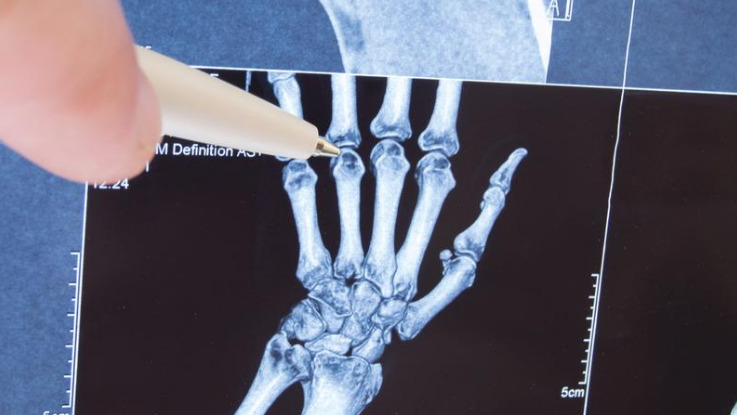

관절염이 생겼는지 확인하기 위해 자신의 손을 검사한 운거 박사는 아무런 변화를 감지할 수 없었다고 합니다. 어린 시절 어머니와 친인척들이 관절염에 걸릴 것이라는 이야기는 사실과 달랐다고 말하고 있죠.